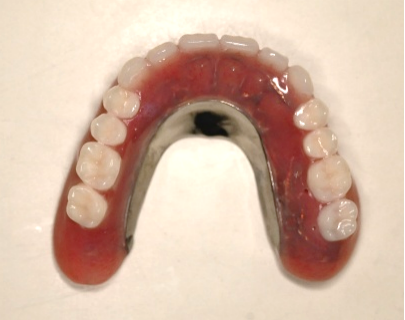

【マグネット式総入れ歯】

上顎

下顎